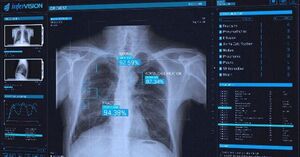

وی ضمن اشاره با اینکه آن دسته از بهبود یافتگان کرونا که دچار عوارض ریوی دراز مدت میشوند، حتما باید تحت نظر پزشک قرار گیرند، ادامه داد: کسانی که کووید ۱۹ را پشت سر گذاشته باید از طریق اسکن نسبت به سلامت ریه خود اطمینان حاصل کنند تا در صورت وجود مشکلات ریوی از آن آگاهی پیدا کنند و تحت درمان قرار گیرند.